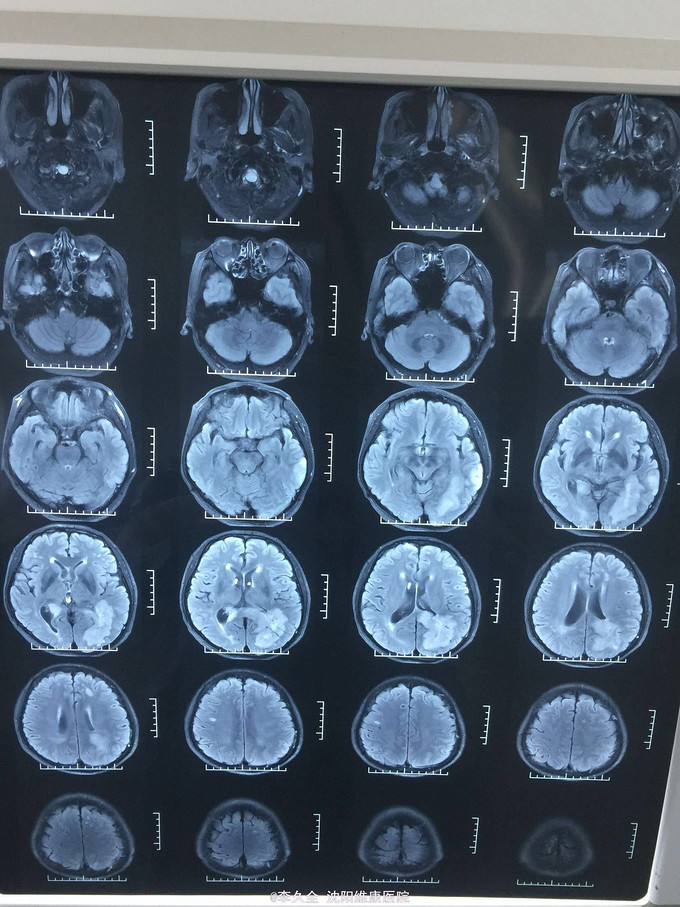

男,62岁,以头晕、视野缺损、记忆力减退、失写、失算7个月入院! 现病史:去年7月出现头晕,就诊于医院,行头CT:代诉未见异常,口服药物无效,后出现右侧视野缺损,走路撞墙、撞门,就诊于当地医院、北京协和医院,考虑“㬵质瘤”,近3个月出现近事遗忘为主,平时写字不会,计算力下降,不认识人! 既往史:2型糖尿病5年!

查体:BP:150/80mmHg,心肺腹无异常。神清,不能言语,失写、失算、失认,双曈孔等大正圆,直径3.0mm,光敏,四肢能够活动,右侧肌张力增高,巴氏征R+L-,颈强3横指,克氏征阳性! 影像MR:

1.颅内占位,胶母可能大! 2.2型糖尿病